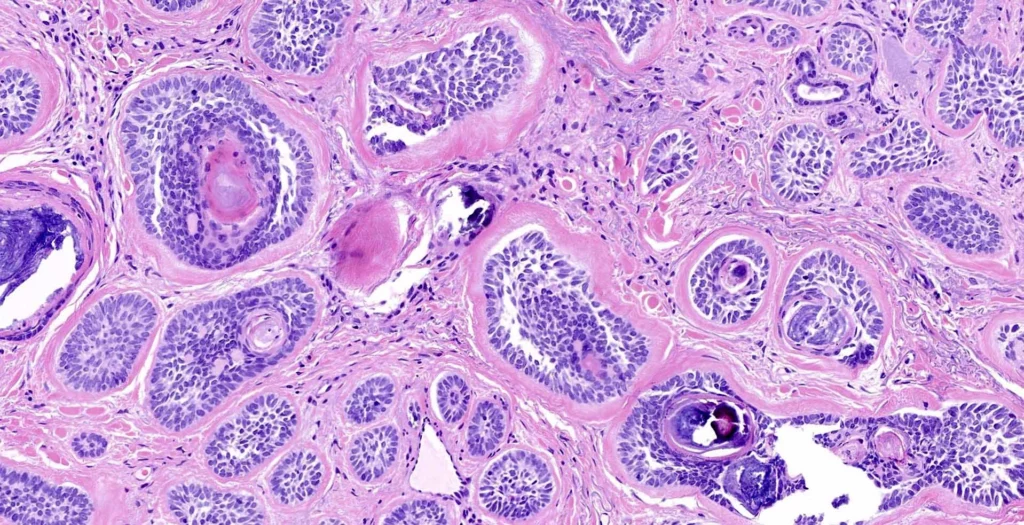

Аденокарциномы классифицируют по нескольким признакам. Один из них – это степень дифференциации клеток:

- высокодифференцированная аденокарцинома молочной железы – состоит из клеток, которые по строению очень похожи на здоровые, делятся относительно редко, реже происходит метастазирование, что обуславливает более благоприятный прогноз для пациента;

- умеренно дифференцированная аденокарцинома молочной железы – клетки имеют меньшую степень дифференциации и чаще делятся, что приводит к более агрессивному течению болезни;

- низкодифференцированная аденокарцинома – опухоль, клетки которой сильно отличаются от здоровых, часто делятся, вследствие чего новообразование быстро растет, распространяется на окружающие ткани и метастазирует в другие органы.

В зависимости от того, из клеток какой структуры развилась опухоль, различают:

- инвазивные и неинвазивные протоковые аденокарциномы (из клеток молочных протоков);

- инвазивные и неинвазивные дольковые аденокарциномы (из клеток долек молочной железы).

Особый тип опухоли – скирозная аденокарцинома, в строении которой преобладают стромальные элементы (это соединительная ткань, нервы, сосуды), а опухолевых клеток немного и они расположены между ними цепочками.